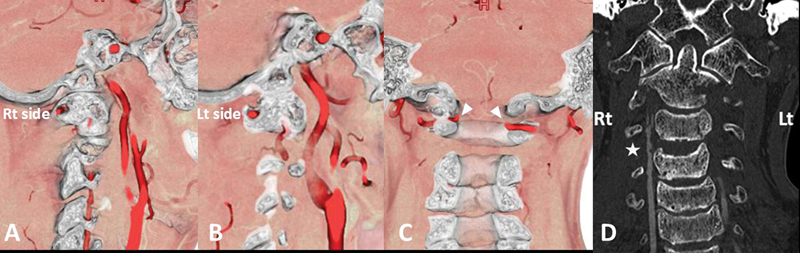

后Ponticulus posticus (PP),也被称为弓形孔,是寰枢椎(C1)的一种解剖变异,是寰枢-枕后膜的骨化,椎动脉(VA) V3段穿过寰枢椎后膜。PP患者在C1侧块内放置多轴螺钉被认为是有风险的,因为可能存在VA损伤的风险。我们报告一例双侧PP,后路固定治疗不稳定的上颈椎损伤。患者,70岁男性,持续跌倒引起的不稳定上颈椎损伤(外伤性C2椎体滑脱伴C3-4小关节单侧脱位)。在最初的保守治疗后,在亚急性期进行了后路固定手术。术前图像显示双侧PP存在。因此,放弃了将螺钉置入C1侧块的原计划,改为将椎板钩置入一侧,将螺钉置入另一侧的C1后弓。他的术后过程很顺利,受伤后27天他被转移到康复医院。在伴有PP的上颈椎不稳病例中,必须根据损伤程度和VA病程逐一考虑固定方法。

Ponticulus posticus (PP), also known as arcuate foramen, is an anatomical variation of the atlas (C1), which is an ossification of the posterior atlanto-occipital membrane and through which the V3 segment of the vertebral artery (VA) runs. Placement of a polyaxial screw in the C1 lateral mass is considered risky in those with PP because of possible risk for VA injury. We report a case with bilateral PP in which posterior fixation for unstable upper cervical spine injury was performed. The patient, a 70-year-old man, sustained a fall-induced unstable upper cervical spine injury (traumatic C2 spondylolisthesis with unilateral dislocation of the C3-4 facet joint). Following initial conservative treatment, a posterior fixation surgery was performed in the subacute phase. Preoperative images revealed the presence of bilateral PP. Therefore, an original plan to place the screws in the C1 lateral mass was discarded, and instead, placement of the laminar hook on one side and placement of the screw into the C1 posterior arch on the other side was performed. His postoperative course was uneventful, and he was transferred to a rehabilitation hospital 27 days after the injury. In cases of upper cervical spine instability with concomitant PP, it is essential to consider the fixation method based on the extent of the injury and the course of the VA on a case-by-case basis.